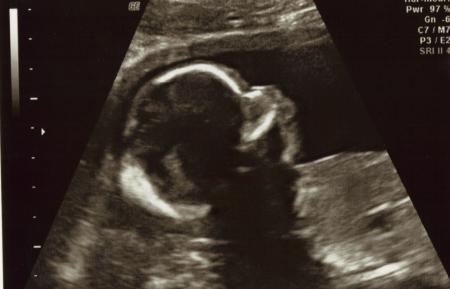

hier zuerst das bild von gestern von der fä nicht sooo toll ...

Bild zu Meine beiden ... - Forum für März - Mamis